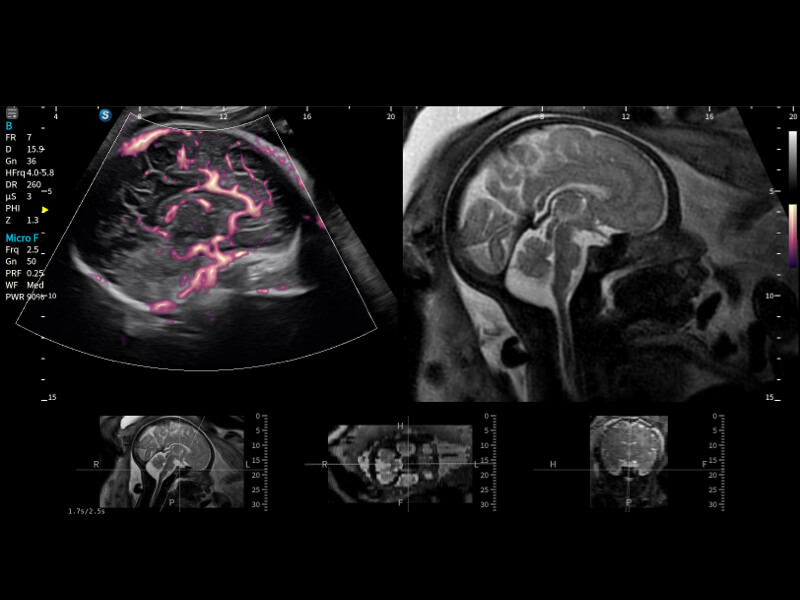

在传统血流的基础上优化扫查和算法策略,能够更好的抑制组织信息,提炼红细胞运动信息,得到更高帧频,高灵敏度和分辨率的血流信号,还原更真实的血流动力学。

通过光照模型,使二维血流显示出立体的效果,增加血流的敏感性、成束性,减少外溢。可以和其他不同的血流技术联合使用,融合不同技术的优势。轻松应对微小血管,增强血流的立体效果,提升视觉敏感性。